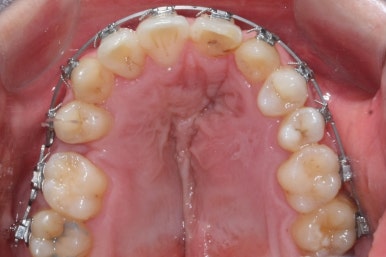

악궁확장이 시작될 시점과 악궁확장을 다 진행했을 시점의 비교입니다.

확실히 좁아져 있던 가로 넓이가 넓어진 것을 볼 수 있습니다.

악궁확장장치는 바로 제거할 경우 다시 원상태로 폭이 좁아질 수 있으므로 3~6개월은 유지해야 합니다.

만약 치아교정 없이 악궁확장장치만 사용한다면 유지장치가 매우 중요하게 됩니다.